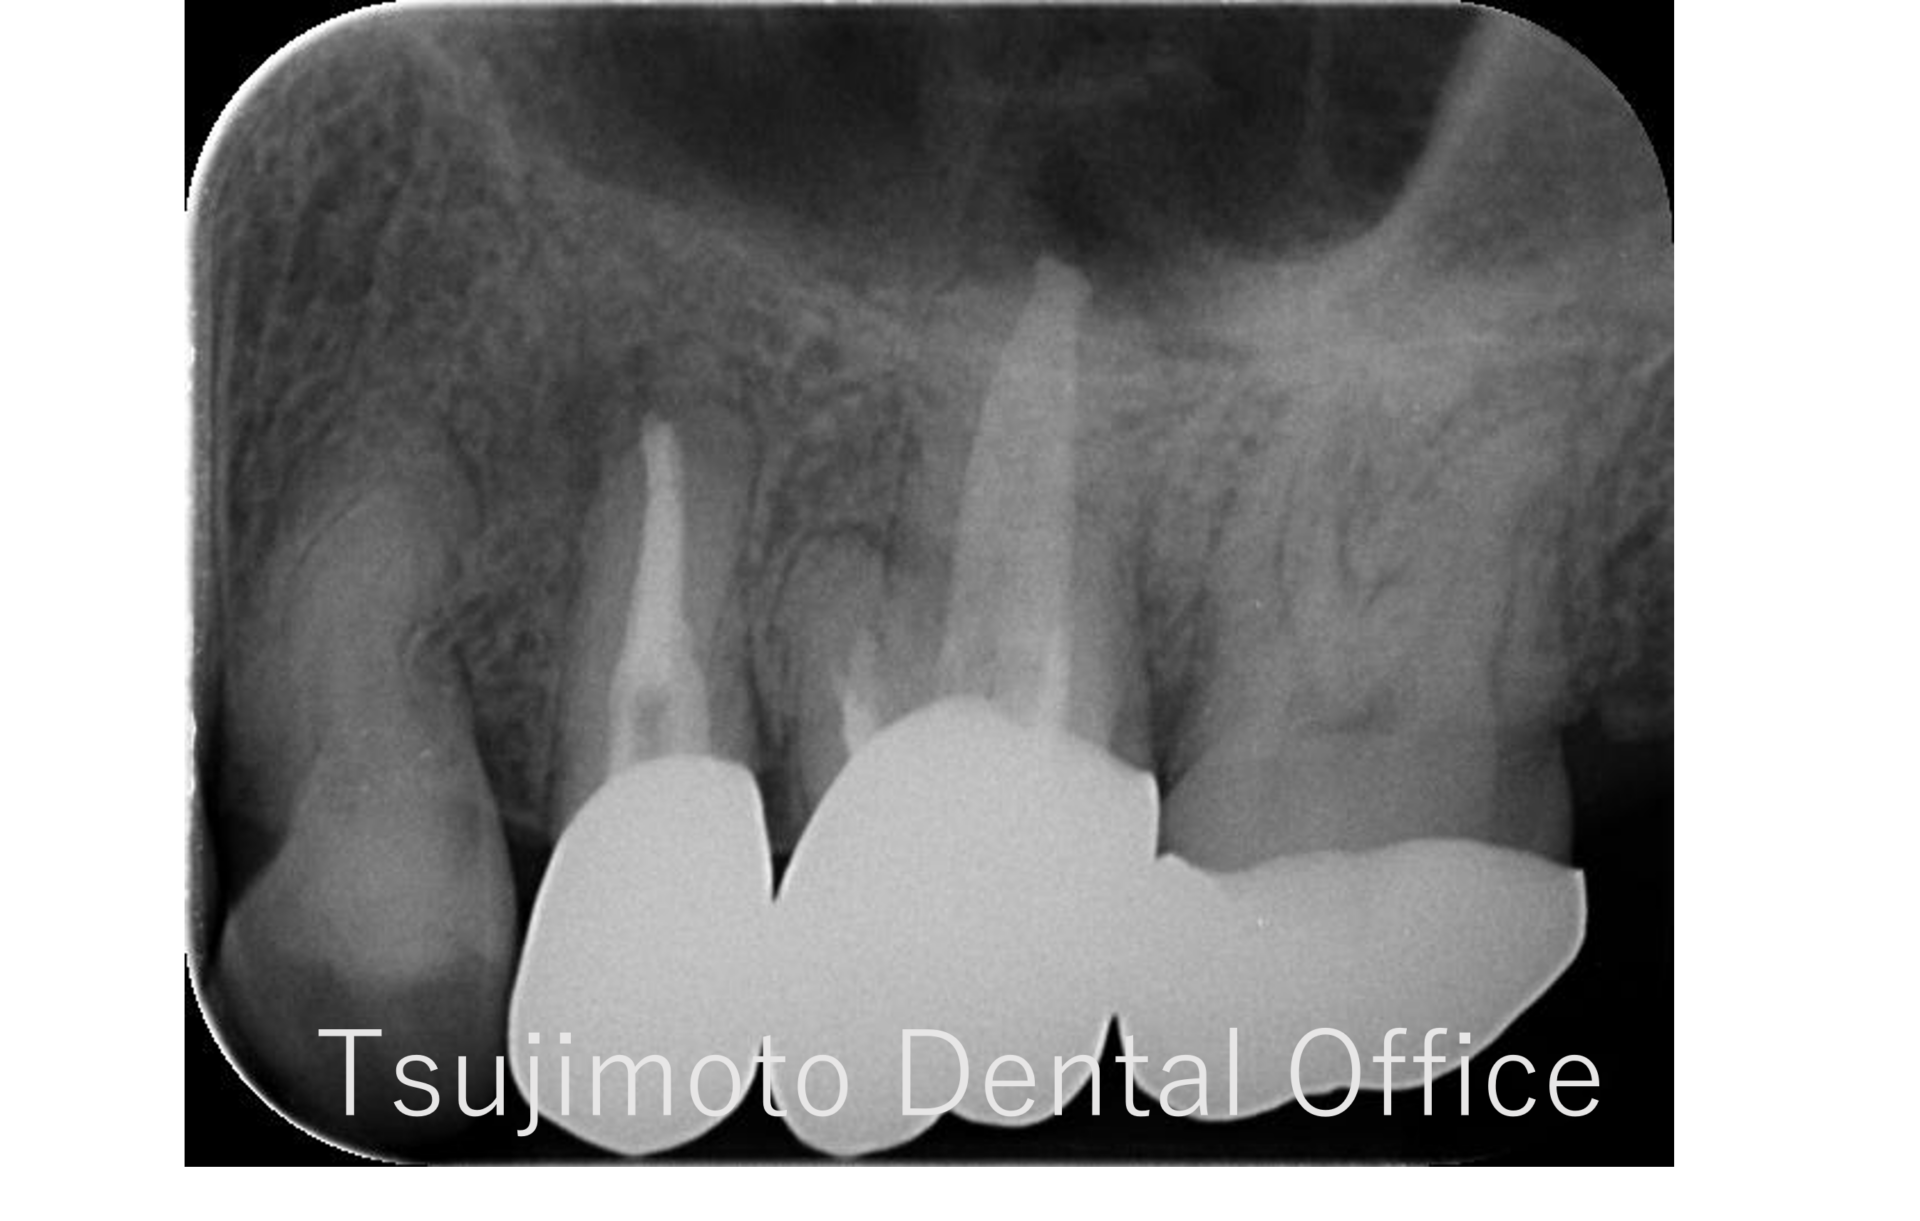

根管治療

大きな病変が出来ている大臼歯の根管治療

Before

After

| 年齢 | 58歳 |

|---|---|

| 性別 | 女性 |

| 治療期間 | 約3カ月(冠除去~根管治療治療3回、その他3回) |

| 治療方法 | マイクロスコープを使用した根管治療、レジン築造、e-maxクラウン |

| 治療費用 | 約40万 |